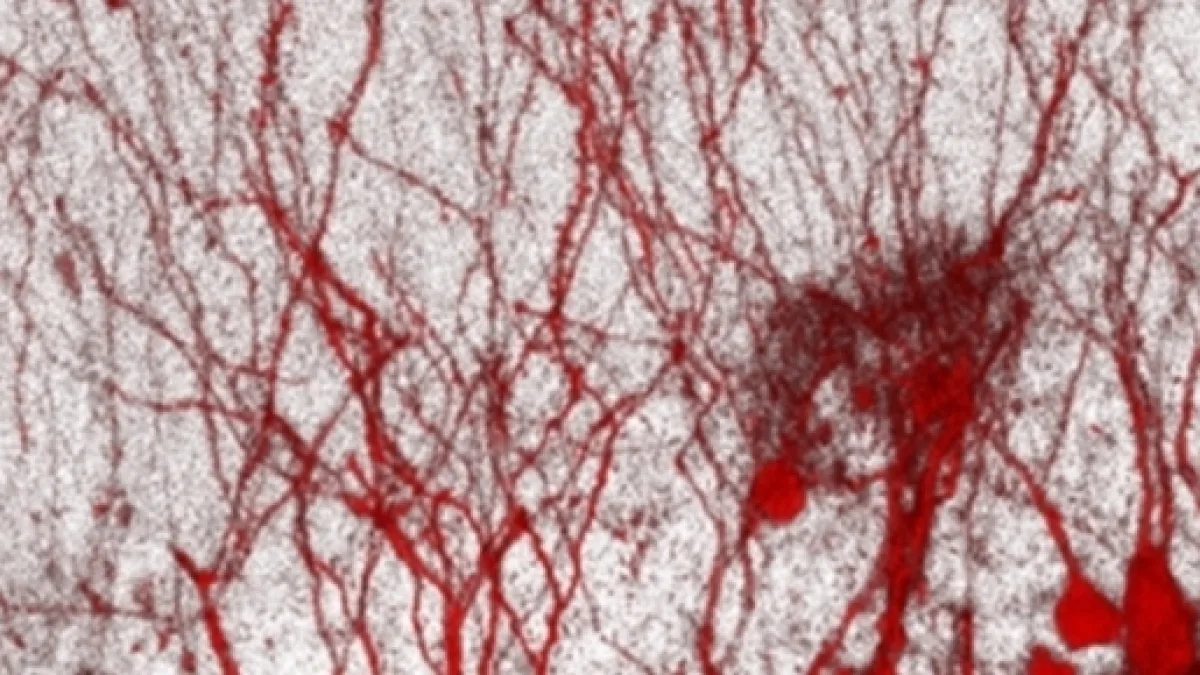

Il gruppo, guidato da Davide De Pietri Tonelli, spiega che il cervello comprende alcune aree, dette nicchie neurogeniche, in cui ii neuroni vengono di continuo generati dalle cellule staminali, che sono cellule totipotenti indifferenziate, capaci cioè di trasformarsi in qualsiasi tipo di cellula. Se i nuovi neuroni vengono danneggiati durante la loro formazione si perdono importanti facoltà cognitive, si rischia la depressione e si tende in maggior misura a sviluppare malattie neurodegenerative come Alzheimer o Parkinson. Le cellule staminali vengono dunque indirizzate a trasformarsi in neuroni da alcuni meccanismi molto difficili da interpretare.

L'equipe dell’Iit con il prof.Tonelli, ha finalmente decifrato il codice genetico che permette alle cellule staminali di trasformarsi correttamente grazie al genoma spazzatura, identificando 11 molecole alla base del processo di indirizzamento. Nel nostro codice genetico il 98% del genoma è dato da sequenze fino a poco tempo fa erano considerate di scarto mentre si è scoperto che il 70% di questi tratti che sembrano non sense sono invece fondamentali per la regolazione dei processi biologici. La "spazzatura"' può essere utilizzata ora in diversi campi terapeutici, perchè potrebbero essere sosituiti i neuroni danneggiati da malattie o traumi, impiantando cellule nervose nuove ottenute dalle staminali.